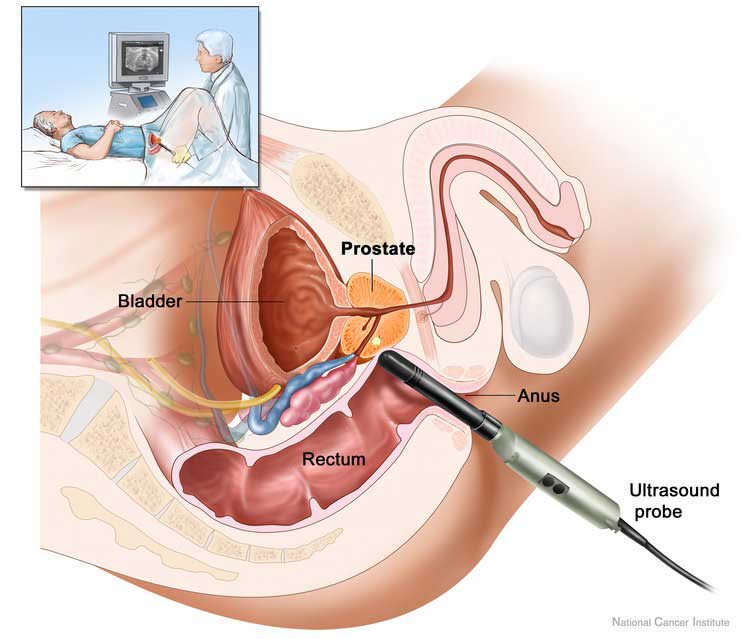

Καμία τεχνική δεν είναι πανάκια, διαβεβαιώνω με την εμπειρία και τη γνώση 30 και πλέον χρόνων. Συνεχίζω ο ίδιος να εκπαιδεύομαι σε νέες τεχνικές, καθώς π.χ η ρομποτική χειρουργική υπερέχει σε συγκεκριμένη κατηγορία ασθενών. Ωστόσο, επιλέγω π.χ την παλιά, «ανοιχτή τομή» για μια επέμβαση 7΄ λεπτών αντί για μιας λαπαροσκοπικής, διάρκειας μιάμισης ώρας με ό,τι αυτό συνεπάγεται για τη νάρκωση και το κόστος εκ μέρους του ασθενούς. «Εκσυγχρονίζομαι» με ιστοσελίδα διότι η εποχή το απαιτεί, αλλά παραμένω «κλασικός» στη θεωρία, ότι δεν κάνει η τεχνική τη διαφορά, αλλά η γνώση, με την προϋπόθεση βεβαίως, ότι γνωρίζει ο ιατρός όλες τις τεχνικές και δεν κατευθύνει. Για άλλες περιπτώσεις είναι εντυπωσιακά τα αποτελέσματα της λαπαροσκοπικής χειρουργικής και για άλλες η διαδερμική ή η ενδοσκοπική προσέγγιση. Ειδικά στη λιθίαση, η ενδοσκοπική ουρητηροσκόπηση, μας «έλυσε τα χέρια» για την πλειοψηφία των περιπτώσεων αφαίρεσης λίθου και ειδικότερα για τα παιδιά και τους ασθενεις με μεταμοσχευθέντες νεφρούς .